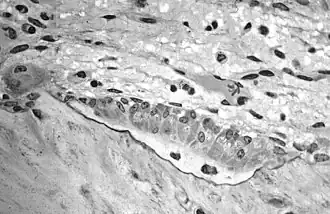

![]() Imagen tomada con un microscopio óptico de un osteoblasto teñido con Giemsa. | ||

Los osteoblastos se disponen en el frente formador de hueso, en una capa epitelioide de células cuboideas o cilíndricas bajas. El núcleo, con nucléolo único, está muy desarrollado, situado con frecuencia en el extremo de la célula más distante de la superficie ósea. Además contienen un aparato de Golgi bien desarrollado, con numerosas mitocondrias, con abundante retículo endoplasmático rugoso que confiere un color intensamente basófilo al citoplasma.